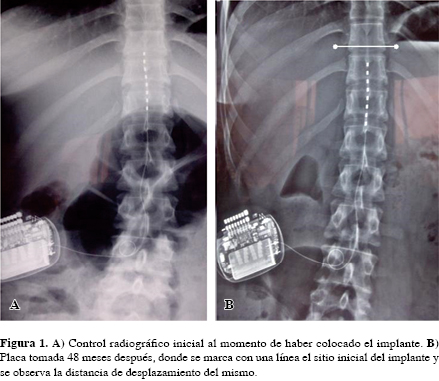

Adolescente de 15 años que presentaba dolor de dos años de evolución en la pierna derecha a nivel del tobillo, de tipo ardoroso, quemante, irradiado desde la rodilla hasta el pie, con una intensidad inicial de dos y actual de 10 puntos, alodinia de la región maleolar y, además, movimientos involuntarios de los dedos primero y segundo, así como dolor a la flexión y extensión del tobillo, edema periarticular, sin fiebre ni rash y con el antecedente de enfermedad de Lyme (Western-Blot IgG versus Borrelia burgdorferi en suero positivo, en LCR negativo); el resto de la exploración física sin datos anormales. La exploración neurológica mostró alodinia térmica dinámica, así como hiperpatía en todo el pie y tobillo, reflejo aquíleo aumentado, flexión y extensión del tobillo disminuidas y dolorosas; la valoración ortopédica sin concluir patología osteoarticular, por lo que se envió a clínica del dolor, donde se diagnosticó como "síndrome de dolor regional complejo tipo II" debido al cuadro clínico y electromiográfico (Tabla 1). Se inició tratamiento farmacológico y de terapia física y ocupacional, sin respuesta favorable. La valoración sicológica reportó adolescente con excesos cognitivos como sobregeneralización, locus de control externo, catastrofización, déficits conductuales: dificultad en habilidades de comunicación y adherencia terapéutica; esto último había sido reforzado por los padres. Se inició terapéutica con los componentes de relación, sicoeducación y sensibilización de su padecimiento, reestructuración cognitiva y autorregulación, habilidades de comunicación, solución de problemas y moldeamiento. Se inició protocolo para estimulación de cordones posteriores con prueba de colocación de electrodo octapolar (Octrode de Advanced Neuromodulation Systems) de forma percutánea, a nivel de T10-12 utilizando los electrodos 3+ y 4- con 30 Hz de frecuencia, 150 ms de ancho de pulso, 8-14 mA de tolerancia a través de la plataforma computarizada de programación (Rapid Programmer de Advanced Neuromodulation Systems), el cual se mantuvo por siete días de forma ambulatoria y seguimiento telefónico diario, con resultado positivo, ya que el dolor se mantuvo controlado en un EVA de 1 a 2 puntos durante sus actividades cotidianas. Se realizó implante definitivo con electrodo octapolar (Octrode de Advanced Neuromodulation Systems) a nivel de T10-T12; se implantó generador Eon (Advanced Neuromodulation Systems). La intensidad del dolor después del implante fue de EVA 1 a 2. Seguimiento: 60 meses, donde ha presentado cuatro exacerbaciones. La primera se resolvió agregando tramadol de liberación controlada 100 mg cada 12 horas y antibioticoterapia por siete días. La segunda se debió a que durante el seguimiento la paciente ha continuado con su crecimiento axial, de aproximadamente tres centímetros, con lo que el electrodo se ha desplazado aproximadamente 150 mm (Figura 1), por lo que se tuvieron que modificar los parámetros de estimulación, donde el electrodo positivo se cambió a 1+ 2-; el resto de los parámetros no se modificaron. La tercera y cuarta exacerbaciones se presentaron de forma espontánea con una diferencia de 12 meses entre cada una y requirieron de hospitalización para utilizar opioides intravenosos, con adecuada respuesta después de tres días; en ambas no se modificó la programación y se continuó con la medicación establecida antes del episodio. En general, el control del dolor ha sido muy aceptable, aunque el generador está encendido las 24 horas del día, ya que si lo apaga, el dolor se incrementa.

En nuestro país no hay experiencia en el manejo del dolor por enfermedad de Lyme, pero en una revisión crítica de la literatura optamos por seguir lo reportado por Mearini,17 donde implantan un estimulador a un paciente adulto con la misma patología y tienen un buen resultado a lo largo del tiempo; éste es el primer reporte de caso sobre este procedimiento. Antes de implantarlo, valoramos su situación sicológica debido a que es una adolescente. Con la intervención sicológica se tuvo una buena respuesta, pues se pudo controlar y modificar la idea irracional del proceso cognitivo; a pesar de presentar catastrofización del dolor, tuvo una buena aceptación; debido a esto, se decidió la colocación del estimulador. Lamé18 reporta que las ideas de catastrofización del dolor no impiden la colocación de este tipo de implantes y no van a afectar el resultado final en cuanto al control del dolor. La estimulación de cordones posteriores ha sido estudiada ampliamente para el manejo del dolor crónico neuropático, principalmente en adultos; incluso los reportes antes mencionados son en pacientes adultos. Por ello, el punto central de este caso es la edad de la paciente al momento de colocar el implante: en ese momento tenía 15 años y una estatura de 1.50 m; durante el seguimiento (60 meses) ha aumentado 3 cm, con lo que su edad actual es de 20 años y su estatura de 1.53 m; desde hace 12 meses ya no ha habido cambio de dicha medida, por lo que suponemos que ya terminó su etapa de crecimiento. Con este cambio de talla hubo un desplazamiento del electrodo, pero no tan grande como para requerir, por el momento, una recolocación; sin embargo, sí cambió de programación debido a que el electrodo que inicialmente estaba estimulando se alejó de la zona requerida, por lo que se tuvo que modificar. El reporte de Olsson19 describe seis adolescentes y sus dificultades técnicas con los casos, pero no menciona nada sobre los efectos del crecimiento sobre la localización de los electrodos; en sus casos pudo retirar la estimulación, pero en nuestro caso esto no ha sido posible. Concluimos que la estimulación de cordones posteriores puede ser efectiva para mitigar el dolor de difícil control en pacientes adolescentes con enfermedad de Lyme.